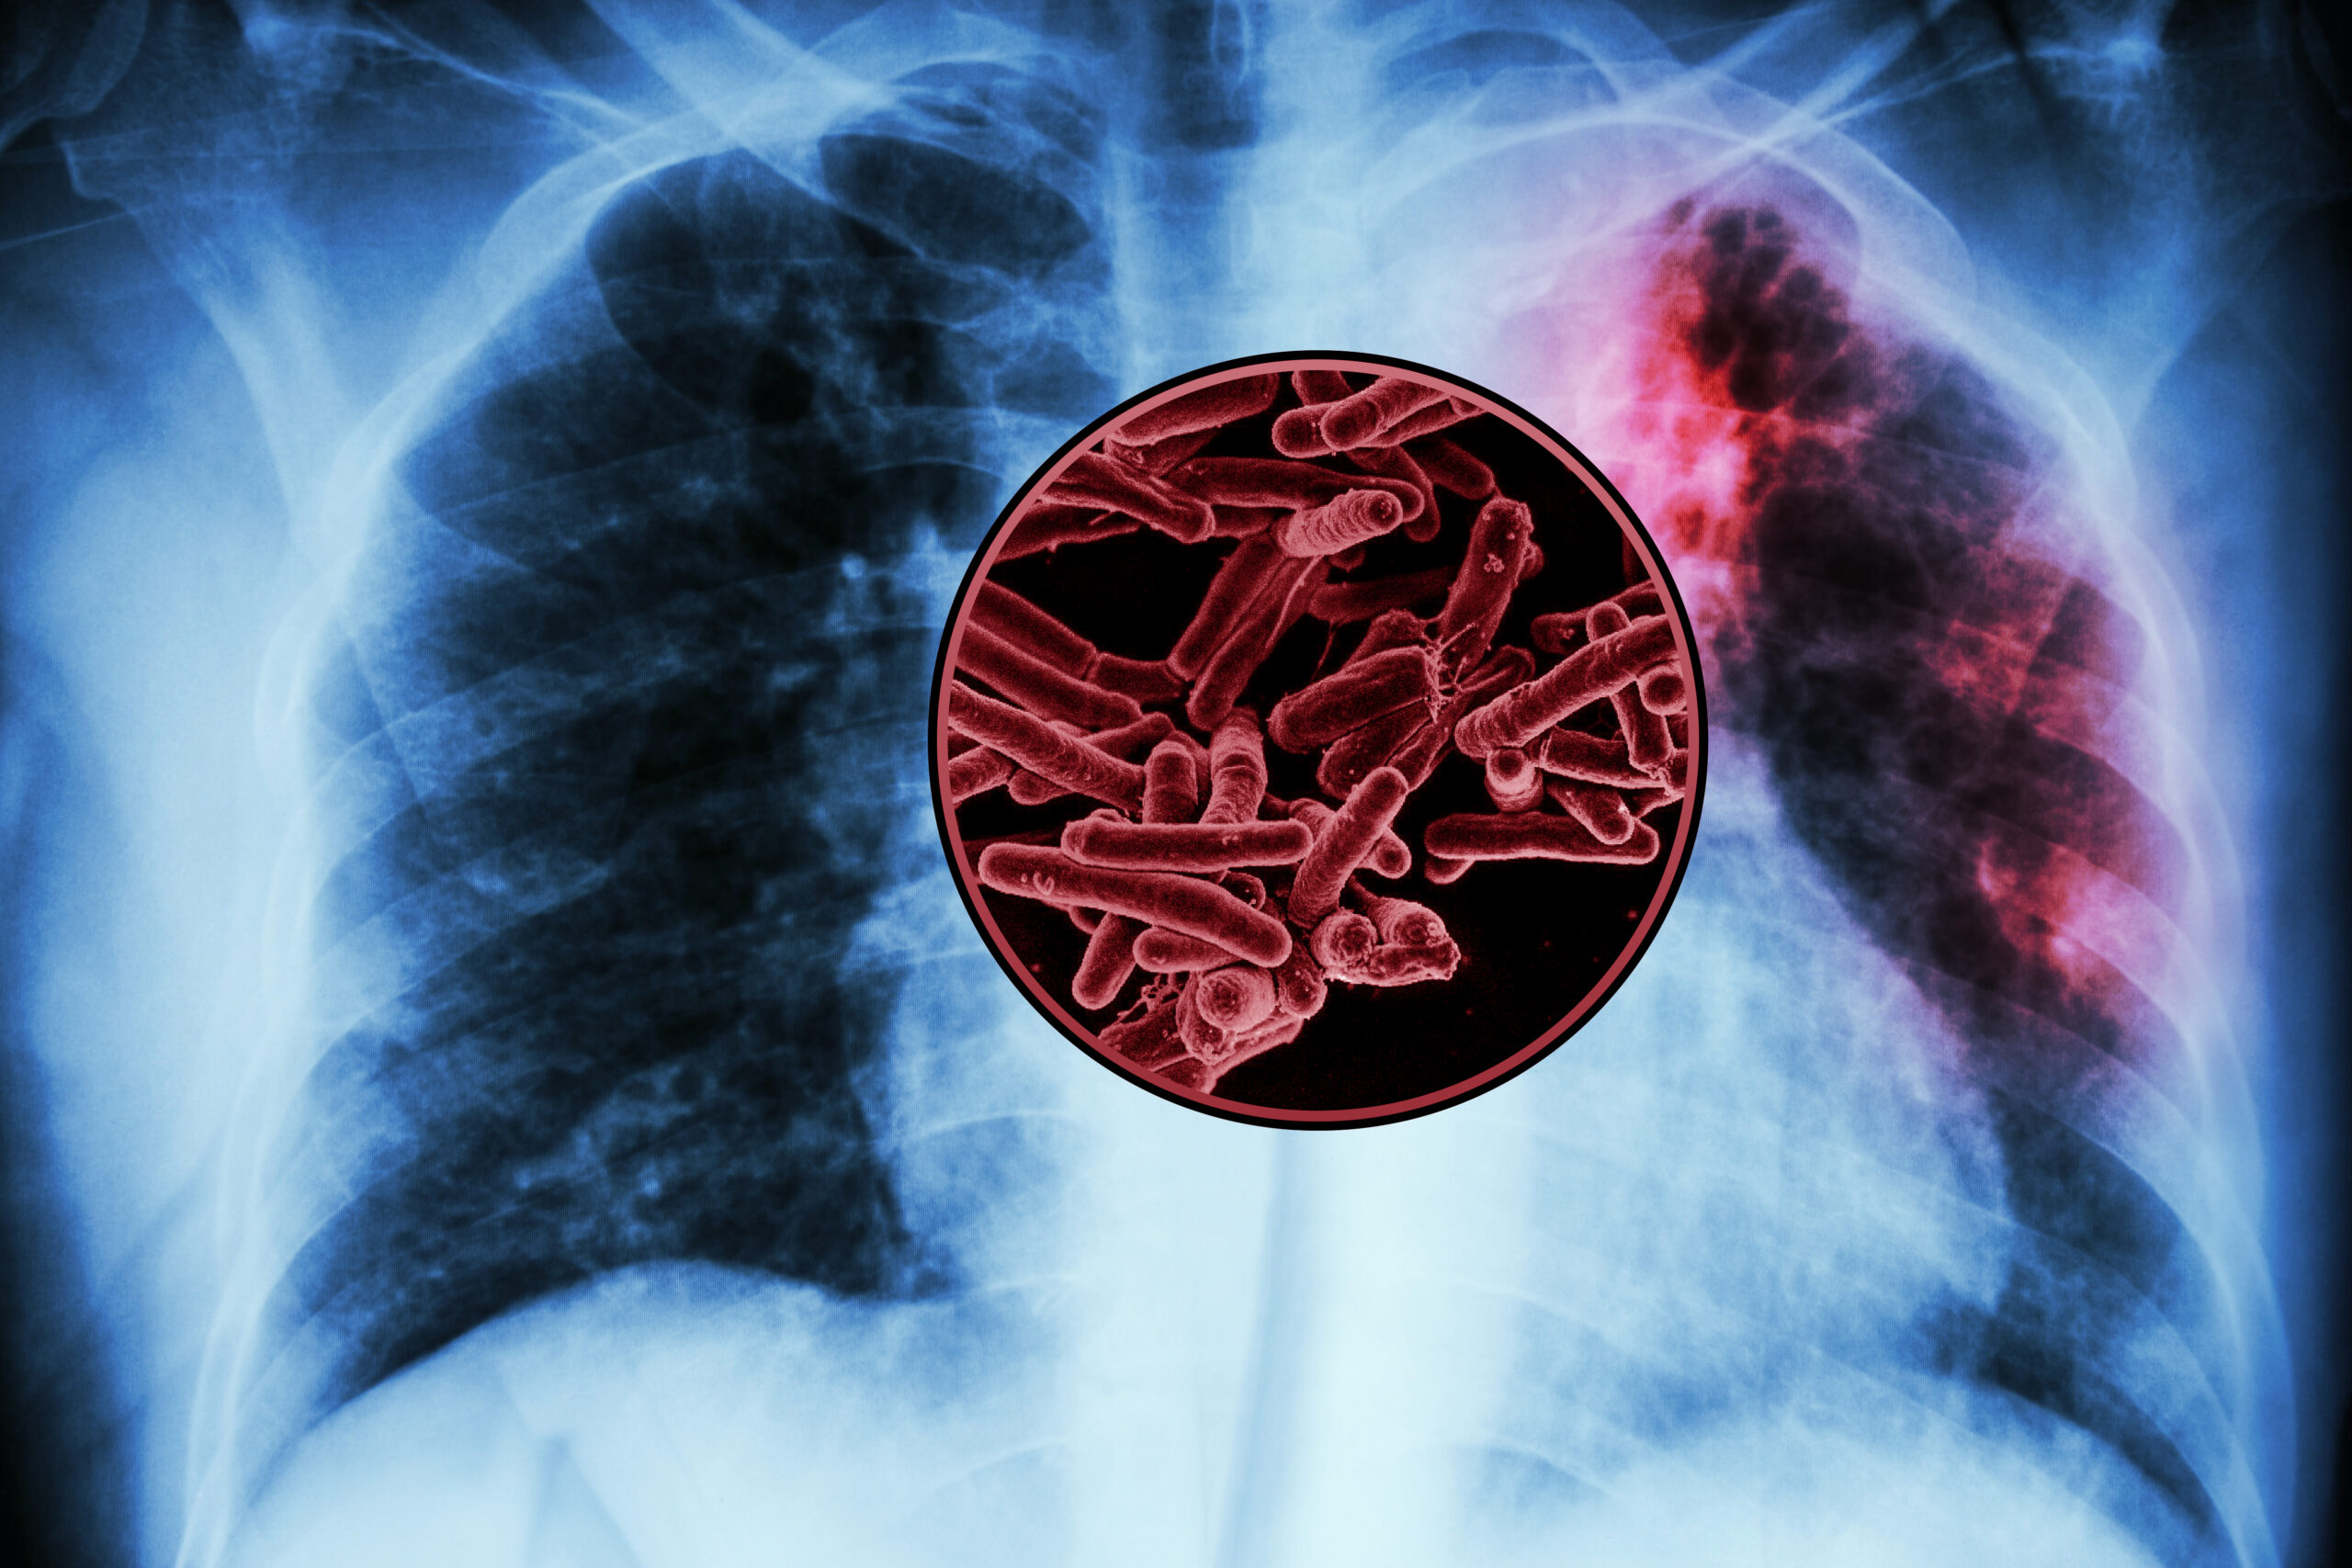

A large-scale screen of tuberculosis proteins has revealed several possible antigens that could be developed as a new vaccine for TB, the world’s deadliest infectious disease.